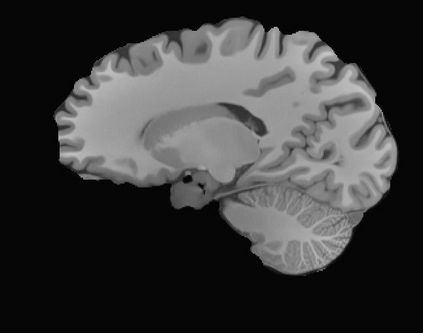

Magnetic resonance (MR) images are often acquired in 2D settings for real clinical applications. The 3D volumes reconstructed by stacking multiple 2D slices have large inter-slice spacing, resulting in lower inter-slice resolution than intra-slice resolution. Super-resolution is a powerful tool to reduce the inter-slice spacing of 3D images to facilitate subsequent visualization and computation tasks. However, most existing works train the super-resolution network at a fixed ratio, which is inconvenient in clinical scenes due to the heterogeneous parameters in MR scanning. In this paper, we propose a single super-resolution network to reduce the inter-slice spacing of MR images at an arbitrarily adjustable ratio. Specifically, we view the input image as a continuous implicit function of coordinates. The intermediate slices of different spacing ratios could be constructed according to the implicit representation up-sampled in the continuous domain. We particularly propose a novel local-aware spatial attention mechanism and long-range residual learning to boost the quality of the output image. The experimental results demonstrate the superiority of our proposed method, even compared to the models trained at a fixed ratio.

翻译:磁共振图像通常在 2D 环境中获得,用于真正的临床应用。通过堆叠多个 2D 切片重建的 3D 体积具有很大的切片间距,导致切片间分辨率低于切片分辨率。超级分辨率是减少3D 图像间隔的有力工具,以便利随后的可视化和计算任务。然而,大多数现有工程都以固定比例对超级分辨率网络进行培训,这在临床场景中不方便,因为MR 扫描的参数各异。在本文中,我们提议建立一个单一的超级分辨率网络,以任意调整比例降低MR 图像的切片间间间距。具体地说,我们将输入图像视为坐标的一个连续的隐含功能。不同间距比率的中间切片可以按照连续域内隐含的显示比例来构造。我们特别提议了一个新的地方觉空间关注机制和远程留置学习,以提高输出图像的质量。实验结果显示我们拟议方法的优越性,即使与所培训的模型相比,也是一种固定比例。